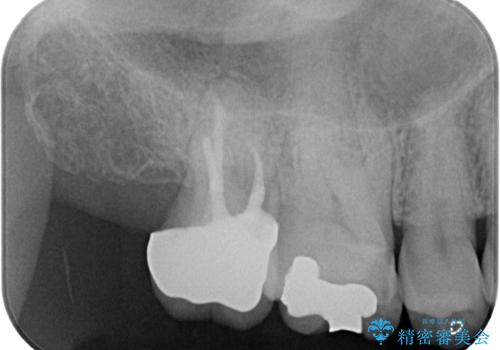

上顎の奥歯は、左右ともに外側に転位しており、特に右上はむし歯の範囲が広く、根管治療も必要な状態でした。

左下の奥歯は状態が非常に悪く、保存は困難と判断されたため、インプラントによる補綴治療が必要でした。

上顎左右の歯をアンカースクリューを用いた部分矯正により位置を修正し、オールセラミッククラウンにて補綴治療を行うこととしました。